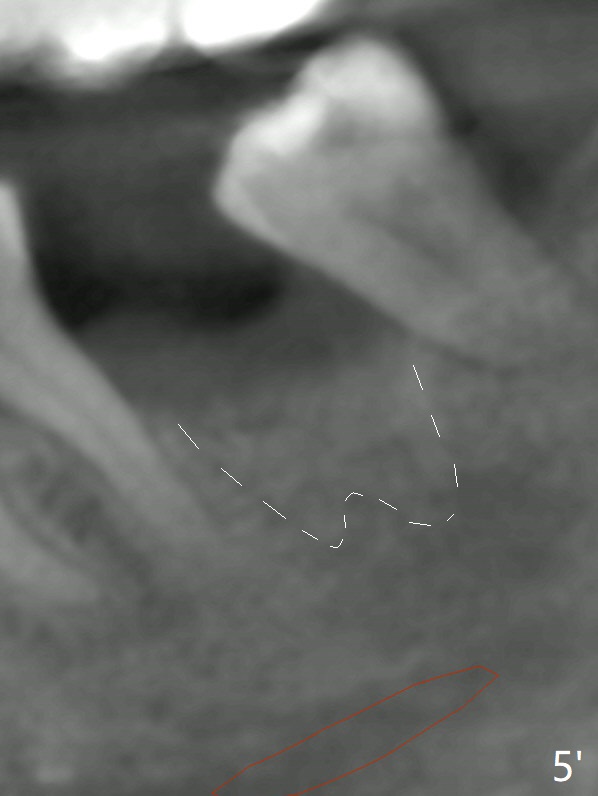

A 49-year-old man returns for #14 and 15 implant impression. The tooth #18 is buccally shifted with mobility, which is incompatible with #14 and 15 restoration. The tooth has to be extracted with socket preservation (Fig.1). A piece of 6-month collagen membrane is used to cover allograft. The socket is healing 9 days postop (Fig.2), probably related to its small wound. Three months and a half postop (Fig.3), CT shows bone healing (Fig.4 sagittal (thin) section, 5 (thick section); 6 (coronal (thin) section). A 5x8.5 mm implant will be placed (Fig.7,8).